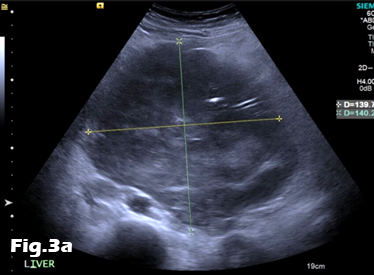

We present the case of a 59-year-old male, previously fit and well who presented to the General Practitioner with a 3 week history of epigastric pain, shortness of breath and unintentional weight loss. On examination, there was evidence of abdominal distension and palpable swelling of left testes. Initial investigation with US of the scrotum revealed dilated (maximally 5.3mm) left pampiniform plexus with retrograde flow on Doppler ultrasound and Valsalva manoeuvre, consistent with an extensive unilateral varicocele (Fig. 1 and 2). Subsequent abdominal ultrasound demonstrated moderate ascites, dilated common bile duct, large right sided pleural effusion and a large 14x14cm solid, vascular epigastric mass. This prompted urgent surgical referral and further cross-sectional imaging (Fig. 3). CT abdomen showed a large soft tissue density retro-peritoneal mass obliterating the portal mesenteric vein circulation and causing the left varicosity (Fig. 4). Ultrasound guided biopsy of the central abdominal mass confirmed a Stage IV Mantle cell Lymphoma.

Figure 3:A, B: Abdominal ultrasound images revealing the presence of a heterogeneous epigastric mass demonstrating internal vascularity on Colour Doppler imaging.